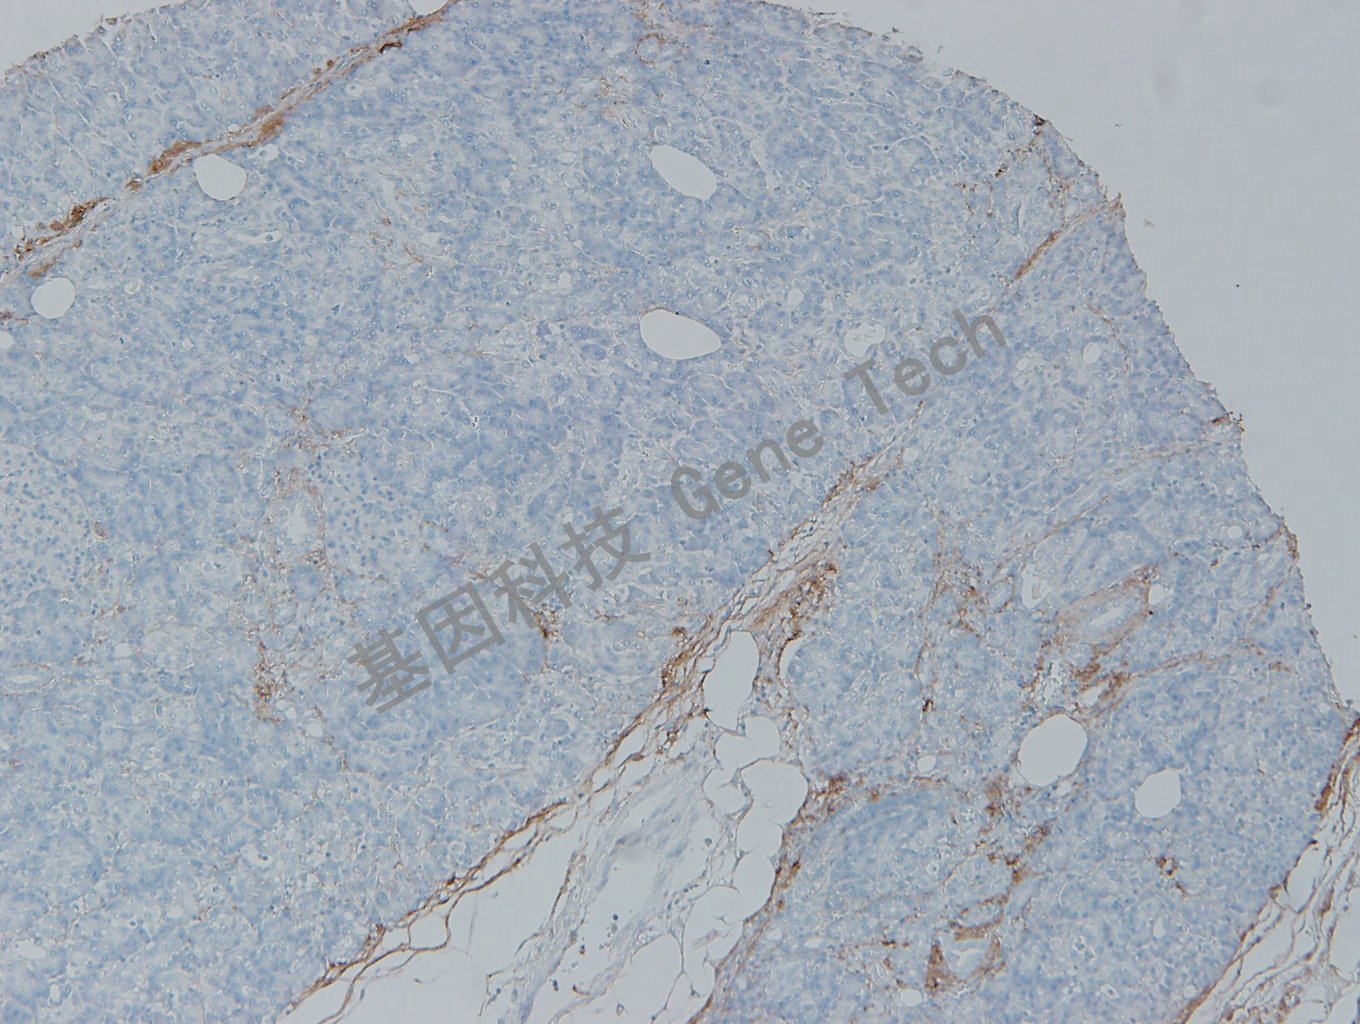

膀胱石蜡切片,用CollagenTypeI(GT2401)染色,细胞浆阳性,DAB显色。

胰腺石蜡切片,用CollagenTypeI(GT2401)染色,细胞浆阳性,DAB显色。

肝石蜡切片,用CollagenTypeI(GT2401)染色,细胞浆阳性,DAB显色。